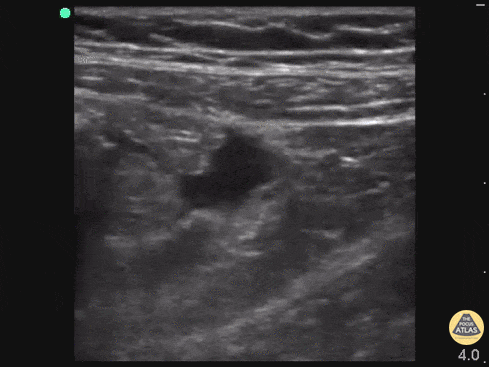

15 year old female with no PMH with 3 days of RLQ abdominal pain, nausea, vomiting with inability to tolerate PO, RLQ tenderness. Bedside POCUS performed for suspected appendicitis. The psoas muscle and iliac vessels were used as landmarks and free fluid was identified. This prompted closer scanning through the fluid. When the probe was rotated to a sagittal plane, a tubular structure with blind end was identified surrounded by free fluid. CT later confirmed appendicitis and patient went to surgery. Drs. Praneetha Chaganti, Kyle Kelson, Scott Kendall - Kings County/SUNY Downstate Emergency Medicine